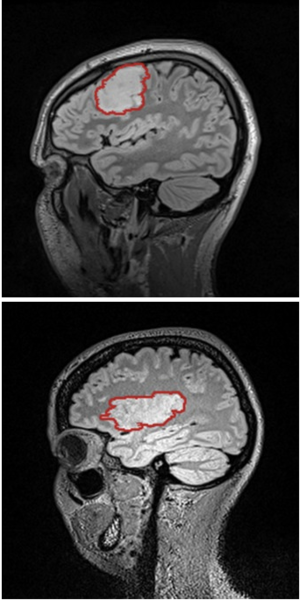

Evaluation of the Novel TSPO Radiotracer [18F] VUIIS1008 in a Preclinical Model of Cerebral Ischemia in Rats

Publication: EJNMMI Res. 2017 Nov 25;7(1):93. PMID: 29177913 | PDF Authors: Pulagam KR, Colás L, Padro D, Plaza-García S, Gómez-Vallejo V, Higuchi M, Llop J, Martín A. Institution: Radiochemistry and Nuclear Imaging, Molecular Imaging Unit, CIC biomaGUNE, San Sebastian, Spain. Abstract: Background: In vivo positron-emission tomography (PET) imaging of transporter protein (TSPO) expression is an attractive and indispensable tool for the diagnosis and therapy evaluation of neuroinflammation after cerebral ischemia. Despite several radiotracers have shown an excellent capacity to image neuroinflammation, novel radiotracers such as [18F] VUIIS1008 have shown promising properties to visualize and quantify the in vivo expression of TSPO. Methods: Longitudinal in vivo magnetic resonance (MRI) and PET imaging studies with the novel TSPO radiotracer 2-(5,7-diethyl-2-(4-(2-[18F] fluoroethoxy) phenyl) pyrazolo [1,5-a] pyrimidin-3-yl)-N, N-diethylacetamide ([18F] VUIIS1008), and (N, N-diethyl-2-(2-[4-(2-fluoroethoxy)-phenyl]-5,7-dimethyl-pyrazolo [1,5-a] yrimidin-3-yl)-acetamide ([18F] DPA-714) were carried out before and at days 1, 3, 7, 14, 21, and 28 following the transient middle cerebral artery occlusion (MCAO) in rats. Results: MRI images showed the extension and evolution of the brain infarction after ischemic stroke in rats. PET imaging with [18F] VUIIS1008 and [18F] DPA714 showed a progressive increase in the ischemic brain hemisphere during the first week, peaking at day 7 and followed by a decline from days 14 to 28 after cerebral ischemia. [18F] DPA714 uptake showed a mild uptake increase compared to [18F] VUIIS1008 in TSPO-rich ischemic brain regions. In vivo [18F] VUIIS1008 binding displacement with VUIIS1008 was more efficient than DPA714. Finally, immunohistochemistry confirmed a high expression of TSPO in microglial cells at day 7 after the MCAO in rats. Conclusions: Altogether, these results suggest that [18F] VUIIS1008 could become a valuable tool for the diagnosis and treatment evaluation of neuroinflammation following ischemic stroke. "Regions of interest (ROIs) were manually defined using the Open Source software 3D Slicer image analysis software (Version 3.6.3)." Funding:

Normalized PET images of [18F] VUIIS1008 and displacements by VUIIS1008 and DPA-714. PET images (ID%/cc) of the coronal and horizontal planes at the level of the lesion from left to right. Summed images of [18F] VUIIS1008 before displacement (0 to 20 min) and after displacement (40 to 60 min) by VUIIS1008 (upper row) and by DPA-714 (lower row). PET images were co-registered with a rat brain atlas for illustration of anatomical regions. |